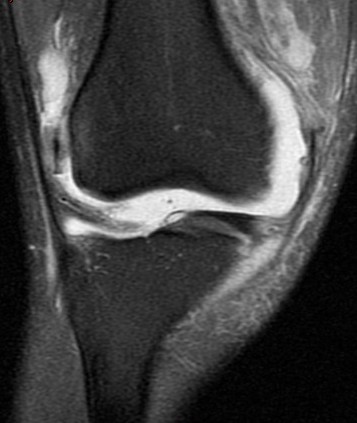

25 y/o twisting injury

Torn mid medial patellofemoral ligemnt, chondral defect of the lateral femoral condyle and medial patella. Displaced chondral fragment adjacent to the lateral femur within the lateral joint space. Also has trochlear dysplasia type B with a subtle supratrochlear spur and an increased tibial tubercle central trochlear distance.

Patellar dislocation